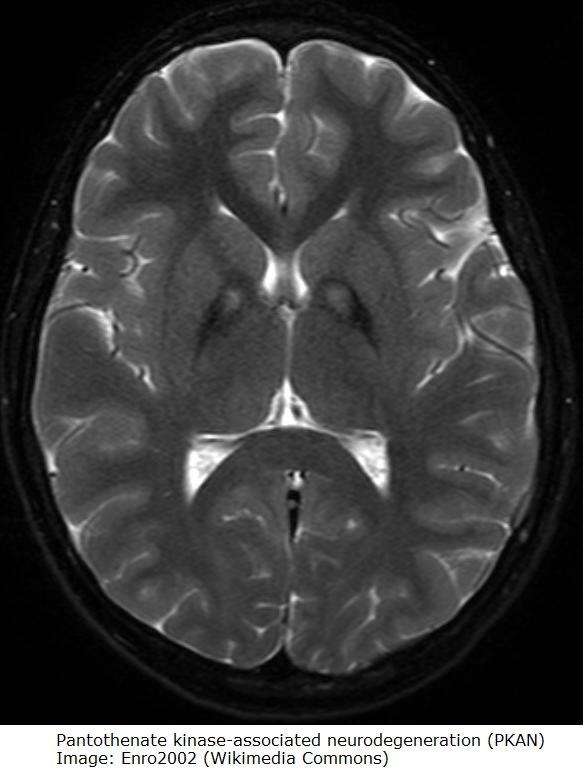

- MR kan vise relativt karakteristiske forandinger ("eye of the tiger")1